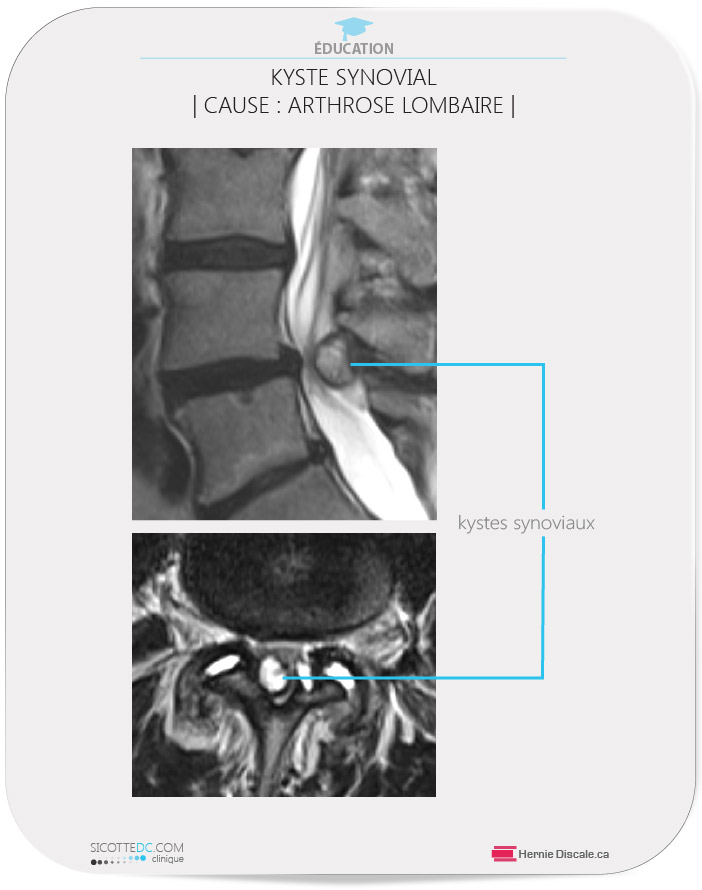

- peut générer un kyste synovial (*2),

KYSTE SYNOVIAL LOMBAIRE | CAUSER PAR L’ARTHROSE FACETTAIRE| (*2)

Suite au disc arthrose lombaire, l’arthrose facettaire lombaire suit comme effet néfaste. L’arthrose facettaire lombaire augment la probabilité de formation d’un kyste synovial. Le kyste synovial est formé par la protrusion de l’enveloppe synoviale autour du joint, soit par un défaut de celle-ci, ou une facette dégénérée. D’autre cause sont les traumatismes, les spondyloses, les spondylolisthésis et la dégénérescence (arthrose) facettaire (5). Les kystes synoviales sont des causes non fréquentes de douleur à la jambe (4).

Il se retrouve majoritairement dans la région lombaire au niveau L4-L5 (1-2).

La majorité des kystes peuvent demeurer asymptomatiques et/ou se résorber. Par contre, une progression rapide peut causer des symptômes de syndrome de queue de cheval ( 42-43-18). Le kyste synovial est directement associé à l’arthrose facettaire. Plusieurs patients réagissent bien aux soins naturels de flexion distraction Cox®. Il est possible d’obtenir un drainage non chirurgical avec des résultats satisfaisants (3).